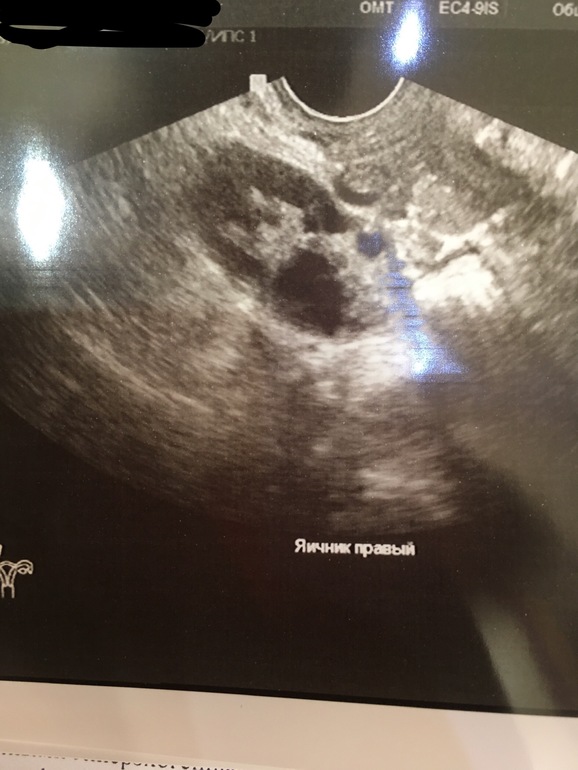

Жт, должно находится на самом яичнике, а тут далеко как-то. Мне на УЗИ показали яичник, и на нём дф, потом она проверяла не жт ли это. Сказала, что кровотока нет, а значит это не жт

Нет. Там ставят мфя Хотя в другом Узи центре поликистоз

А кисту не на правом ставят? Просто тут, что-то не понятное. Мне показывали яичники, круглые, а тут не понятно

Жаль мне фото не дали, я бы показала, как у меня выглядели с фоликулами. Опишу так. Вот как у вас левый яичник, круглое пятно, а на нём тёмные маленькие пятнышко. Вот на них узистка и указала, что это фолликулы. Там их по 4 и 5 штук на каждом яичнике ну и один доминантный 20 мм был. Вот на него и думали, что это жт, но оказался фоликом